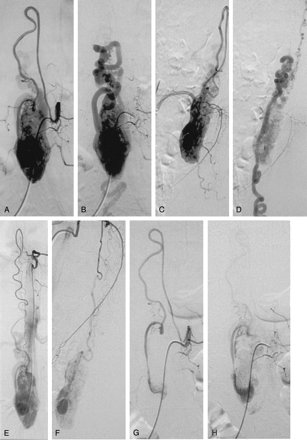

Case 2. Hemangioblastoma of the cauda equina in a 47-year-old woman with VHL disease.

Selective spinal angiography of the left second lumbar artery (A–D) shows the ASA (artery of Adamkiewicz) feeding the tumor (A, early, and B, late phase in anteroposterior view; C, early, and D, late phase in lateral view). Selective angiography of the left T10 intercostal artery (E, anteroposterior; F, lateral) shows an additional supply to the anterior spinal axis from a thoracic radiculomedullary artery. The left T10 intercostal artery also gives rise to a left posterior spinal artery (Lazorthes artery) providing a slight supply to the superior pole of the tumor. Descending anterior and ascending posterior venous drainages are observed. Embolization was performed through the anterior spinal axis from the left second lumbar artery. After embolization, selective spinal angiography of the left second lumbar artery (G–J) shows reduction of the tumoral blush tumor (G, early, and H, late phase in anteroposterior view; I, early, and J, late phase in lateral view).